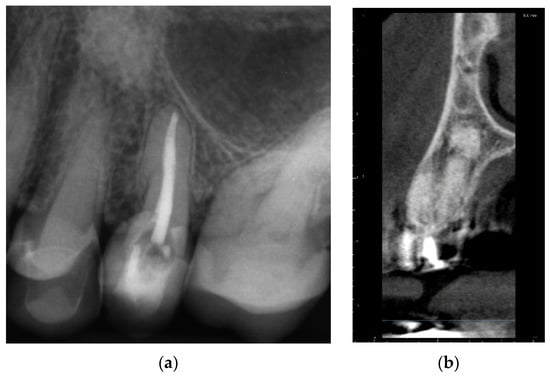

A 72-year-old female patient was referred to an endodontic specialist for the treatment of the maxillary left first premolar (tooth 24) before the surgical procedure of removing a periapical lesion. The endodontic treatment had been initiated by the referring dentist, but it was impossible for the clinicians to localize the buccal root canal under the optical microscope. The medical history revealed controlled diabetes. The patient presented with no complaints. Clinically, there were no pain or sensitivity to percussion or palpation and tooth mobility was not increased. The tooth was restored by the referring dentist with a temporary restoration (composite resin) and showed no response to the pulp sensibility test (cold test). The radiograph and the CBCT (CS 8100 3D, Carestream, 50 × 50 mm) images confirmed root canal obliteration (Figure 19). After discussing a high probability of perforation and further tooth substance loss, an endodontic guide was designed.

Figure 19. Nonvisible root canal system on (a) X-ray and (b) CBCT images (tooth 24).

2.2.2. Case Report—Patient D: Symptomatic Pulp Necrosis with Pulp Canal Obliteration

A 68-year-old female patient reported to the endodontic specialist complaining of acute pain upon percussion of her maxillary first premolar (tooth 24), experienced for several days. The patient was healthy and did not have any general or chronic diseases. The clinical examination revealed tenderness to percussion and a negative response to the pulp sensibility test (cold test). Radiographic images revealed pulp canal calcification and the absence of the canal light (Figure 24). A CBCT scan was performed (CS 8100 3D, Carestream, 50 × 50 mm) and confirmed canal calcification (Figure 25). The palatal canal was found during the first visit. The buccal canal was obliterated. Due to the possible risk of higher tooth substance loss and perforation during endodontic access, we decided to perform the endodontic treatment with guided access.

Figure 24. X-ray image showing the obliteration of the root canal.

Figure 25. The CBCT image confirmed the calcification of the buccal canal.